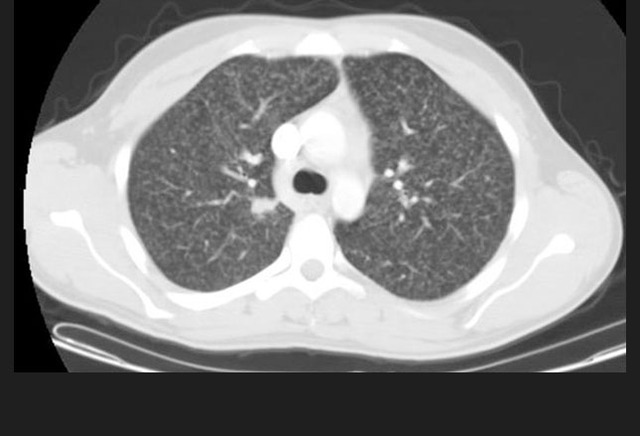

图4. 胸部CT展示了右上肺尖部的病变

除了双上肺肺气肿外,下列哪项增加患者感染结核的风险?

A、糖尿病;

B、慢性肾衰竭;

C、强的松20mg/天的治疗;

D、HIV感染;

E、矽肺。

答案:D、HIV感染